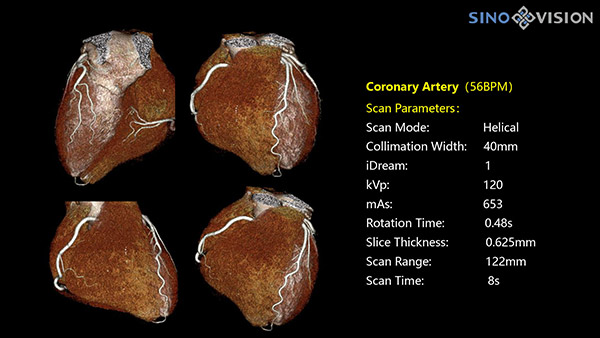

Инновационный 128-срезовый компьютерный томограф SinoVision InsitumCT 568 – это сочетание высокой скорости работы, низкой дозы и максимума возможностей для подавляющего большинства клинических случаев, как в рутинных, так и в углубленных специализированных исследованиях, в том числе педиатрические и кардиологические исследования при сверхнизких дозах.

Полнофункциональная платформа клинической диагностики может точно определять местонахождение и диагностировать общие повреждения качественно и количественно, а также достигать полнофункциональных клинических показателей, включая обширные кардиологические исследования со сверхнизкими дозами лучевой нагрузки.

- Минимальное время одного оборота рентгеновской трубки: От 0.48 до 2 сек

- Коронарный анализ

- Ретроспективный режим сканирования с ЭКГ-синхронизацией

- Проспективный режим сканирования с ЭКГ-синхронизацией

- Режим последовательного сканирования c ЭКГ-синхронизацией и без ЭКГ-синхронизации